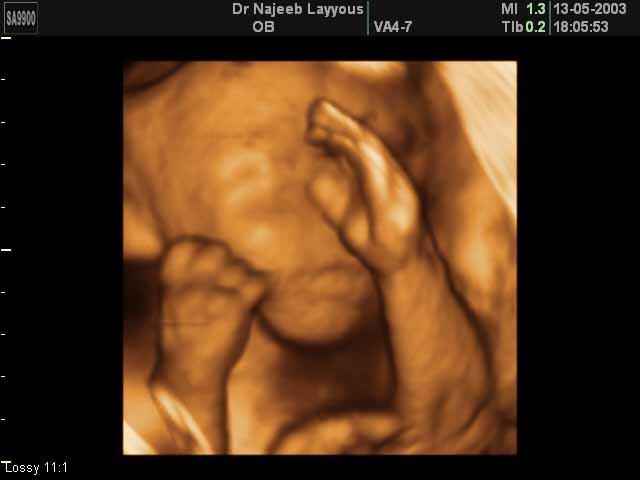

- 3D Fetal Limbs Ultrasound Scan Photos